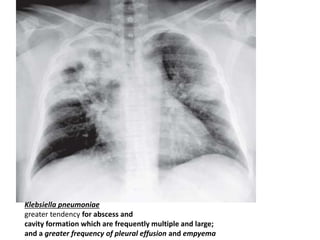

Klebsiella pneumoniae

greater tendency for abscess and

cavity formation which are frequently multiple and large;

and a greater frequency of pleural effusion and empyema

Klebsiella pneumoniae greater tendencyfor abscess and cavity formation which are frequently multiple and large; and a greater frequency of pleural effusion and empyema